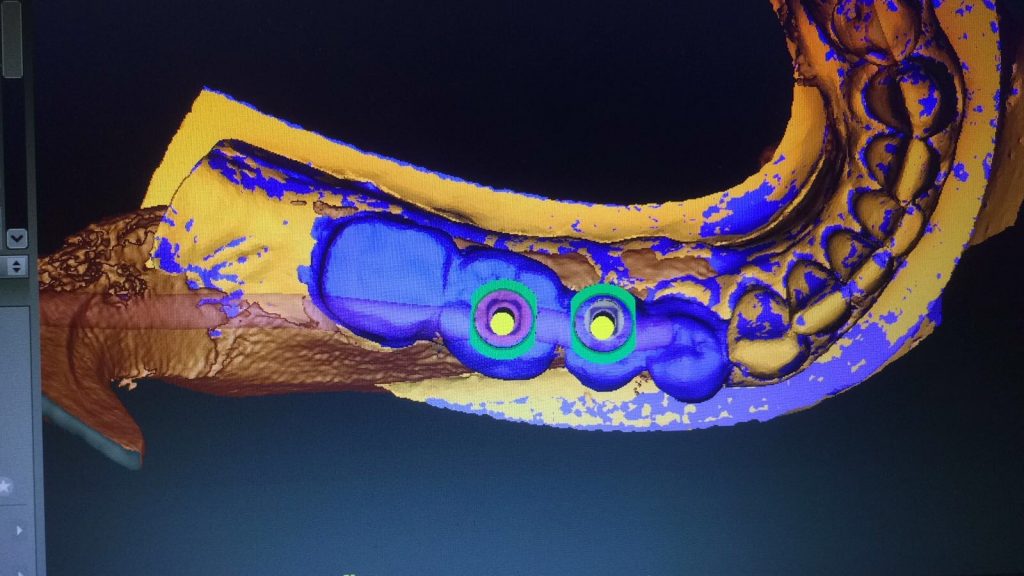

Autores: PRÓLOGO Asimismo, desde el punto de vista pedagógico, el profesional nobel en la materia tiene a su alcance la posibilidad de corregir cualquier posición implantaría en el ordenador, planear los provisionales y plasmarlos en la bio réplica antes de tocar al paciente a operar. Todos estos razonamientos nos llevan a presentar un caso de condiciones muy favorables para poner en práctica estos métodos como primer acercamiento a una Odontología Digital de alta calidad, con medios informáticos, que ya están presentes en la profesión de hoy en día, y será la protagonista única del futuro. Por otro lado, después de numerosos estudios que nos llevan a plantear el “gap” entre implante y pilar(abuttment), como principal responsable de la periimplantitis dado que la microbiota presente en el mismo es imposible de limpiar y en su presencia la cortical ósea reacciona reabsorbiéndose, nos ha llevado a utilizar implantes monobloc ya que los ejes implantarios y protéticos coincidían, y nos permitían su uso. Además, el circonio, ha mostrado a la luz de estudios muy recientes, una preservación y adhesión de los tejidos blandos superiores al titanio, tanto en su tratamiento de superficie de la rosca como a nivel gingival. DESARROLLO Paciente varón de 68 años, con antecedentes de radio/quimioterapia cinco años antes, con Rehabilitación Oral de los cuatro cuadrantes, con una Oclusión Mutuamente Compartida conservada, (REF.8) la que fracasa en el cuadrante 4, 19 años después. El mismo presentaba un puente de porcelana sobre circonio con pilares en 44 y 47, reemplazando el edentulismo de 45 y 46. Se produce la fractura del PM del 44, y ante una endodoncia antigua y corta, se decide implantar las zonas edéntulas, conservando temporariamente los pilares, hasta producida la oseointegración, para entonces también exodonciar el 44. DIAGNÓSTICO Tomamos impresiones del maxilar antagonista, Arco Facial Estático y realizamos montaje del mismo mediante la sistemática ARTEX. Producimos la relajación del músculo Pterigoideo Externo, para obtener la ORC (Oclusión en Relación Céntrica) mediante el método de Laminillas de Long, basado en el concepto de INERVACIÓN RECÍPROCA. Esto nos permitirá montar el maxilar inferior, tanto en su forma de: La primera para practicar la cirugía guiada y comprobar su eficacia, y el modelo de yeso para ser escaneado y confeccionar la GUÍA QUIRÚRGICA. La Biorréplica la obtenemos transformando los archivos DICOM que nos da el CBCT en archivos STL, y a partir de ellos, mediante una tecnología de PROTOTIPADO RÁPIDO, la obtención de un objeto físico en 3D a través de la aglutinación selectiva de una sucesión de capas de polvo. Procedemos a montar la biorrèplica y el modelo de yeso del caso. Podemos verificar la exactitud de las medidas del hueso residual en la bio réplica y compararlas con el scanner. Arrojando un resultado de 8,5 mm de cortical externa a cortical externa. Pudiendo también medir la distancia hasta el dentario. y comparar gracias a la ventana lateral de la biorréplica Dándonos 22mm de distancia. Con lo cual deducimos que implantes de 4,1mm por 12 mm serán perfectamente rodeados de hueso. Medimos también la distancia desde oclusal del antagonista, hasta el hueso desnudo. Lo mismo que, mediante la utilización de la guía radiológica, con un material radiolúcido colocado en gingival de la misma, podemos medir la altura de la encía. Con lo cual podemos calcular la altura del pilar. Es entonces cuando con el programa COC Diagnostix se realiza la programación final: Obteniendo no solo la ubicación, largo, ancho y ángulo de los implantes sino también los provisionales mediante CAD CAM. Ya entonces podemos hacer la práctica quirúrgica en la bio réplica, mediante la guía quirúrgica, instalando los implantes de prueba que no serán los de circonio, ya que la casa no cuenta con ellos, pero si otros de las mismas dimensiones. TRATAMIENTO Entramos ya en la cirugía propiamente dicha. Antisepsia de la zona a operar y zonas anexas. Comprobación del perfecto ajuste e inmovilidad de la G.Q. en boca durante la cirugía. Marcado de la encía y perforación de la cortical. Visión a través de la Guía de la mínima intervención anterior. Comprobación sin Guía. Incisión mínima mesio distal, para apartar y conservar encía queratinizada. Secuencia de drills, perforando a profundidad requerida Observación del Mínimo Trauma Implantes Strauman de Zirconio Monoblock en blíster y montádo en contrángulo reductor. Instalación controlando torque con contrángulo reductor. Comprobación clínica. Comprobación Radiográfica y con Guía. Toma de impresiones, y armado de modelos con técnicas de pasividad protética. Montaje. Resultado de las provisionales ejecutadas por CAD CAM Al no estar conformes con el resultado decidimos desechar dichas provisorias y optar por repetirlas. Nuevas provisorias realizadas mediante encerado convencional. Estado de los tejidos blandos. Provisorias en boca. Oclusión de Estímulo Inmediato. Ref.10: Carga inmediata .Alberto y Diego Bechelli. Comprobación mediante CBCT post operatorio Componentes del equipo (En la próxima presentación, mostraremos las coronas definitivas de porcelana sobre circonio, y la desoclusión provocada por una OCLUSIÓN MUTUAMENTE COMPARTIDA, sobre estos implantes y otros seis mas) REFERENCIAS

FIG: 14-15-16-17-18-19-20

Fig. 14

Fig. 15

Fig. 16

Fig. 17

Fig. 18

Fig. 19

Fig. 20